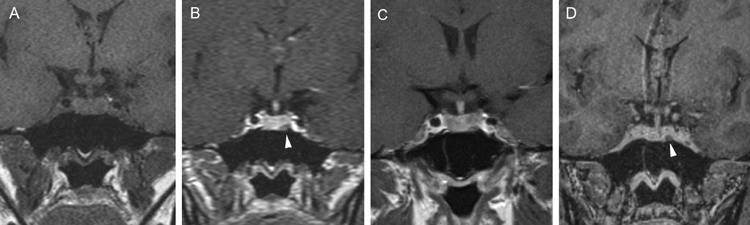

En el caso de los microadenomas, al ser tumores funcionantes, el cuadro clínico y de laboratorio ayuda a definir la localización de la lesión. La glándula pituitaria, considerando el pequeño tamaño de los tumores, puede mostrar forma y volumen normal. En un 20-25% de los casos no se logra demostrar los microadenomas menores de 3 mm, lo que aumenta al 40% en el casos de los adenomas productores de ACTH, en que los exámenes falsos negativos son más frecuentes36-38 (Figuras 11A, 11B, 11C y11D). En este grupo de pacientes es fundamental la utilización de protocolos de examen que incluyan cortes finos coronales de 1 mm en secuencias ponderadas en T1 antes, durante y después de la inyección de Gadolinio, para asegurar la detección de los adenomas, los cuales se contrastan en general más tardíamente que la glándula normal39-41 (Figuras 12A y 12B).

Figura 11A. Microadenoma pituitario productor de ACTH, corte coronal, secuencia T1w, muestra señal homogénea en la hipófisis. B. corte coronal (secuencia dinámica T1w con Gadolinio); se observa nódulo hipointenso de 3 mm (que aun no se refuerza) en cuadrante inferolateral izquierdo de la hipófisis (punta de flecha). C. corte coronal, secuencia tardía T1w con Gadolinio, muestra refuerzo heterogéneo de la glándula, no es posible precisar la ubicación del tumor. D. corte coronal, secuencia volumétrica SPGR T1w con Gadolinio de 1 mm de espesor, que muestra claramente la ubicación del tumor (punta de flecha). Esta secuencia ha mostrado mejores resultados en la evaluación de la enfermedad de Cushing.